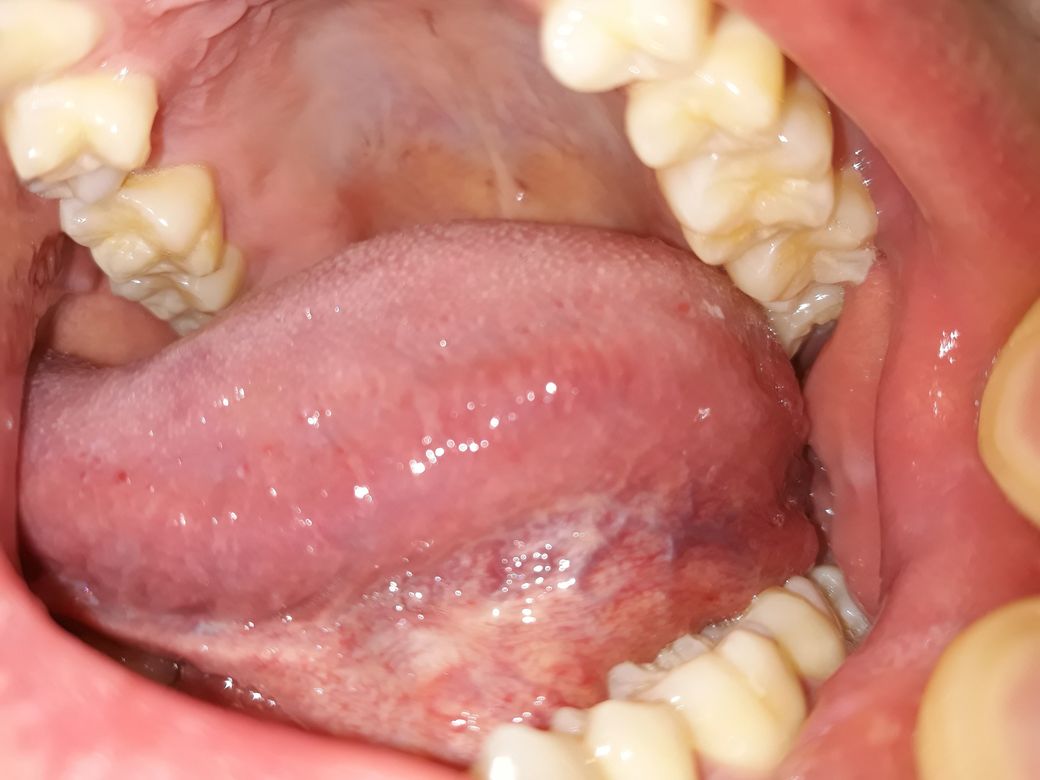

양치하다가 혓바닥 옆쪽 아래를 봤는데 잔핏줄도 많이 보이고 중간에 색깔도 군데군데 누런거같기도한데 만져보니깐 부드럽고 통증이나 불편한건 없습니다. 괜찮은건가요?

• 2번 째 사진

입 구석구석을 살펴보셨네요. 사진 올려주신 것만 봐서는 특별한 이상은 없어 보입니다. 증상도 없으니 괜찮다고 보셔도 되구요.

특별히 현재 통증 및 이물감 등이 있는 것이 아니라면 이상소견으로 보지는 않습니다.

만약 증상발생시는 치과에 내원해 보시는 것을 추천드립니다.